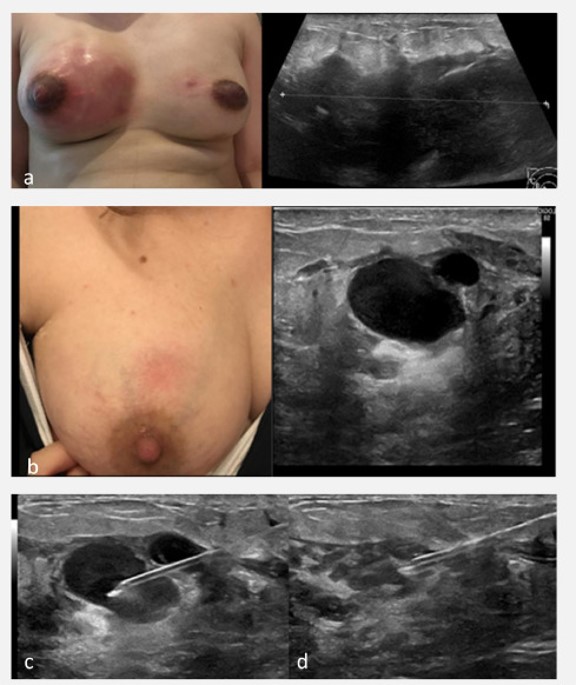

Images 1-3 below demonstrate needle aspiration of an abscess.

Image 1

Image 2

Image 3

Images 1-3: Hu et al 2023